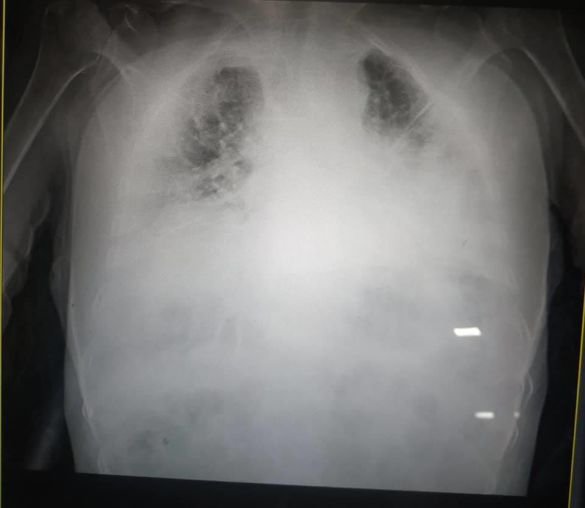

Медики Львова показали, який вигляд мають легені, уражені Covid-19.

Фото уражених коронавірусом легенів Ірина Заславець виклала у Facebook. Орган на знімку перетворився на суцільну світлу пляму.

"Це одні з найстрашніших легенів, які я бачила в житті", - сказала очільниця реанімації клінічної лікарні швидкої медичної допомоги Львова", — написала Заславець у дописі.

Легені померлих внаслідок Covid-19 відрізняються від типового стану і більше нагадують печінку. Усередині легені змінюються через тромби. "Коронавірусну" пневмонію ні з чим не переплутаєш, розповіли паталогоанатоми Львівського обласного моргу.